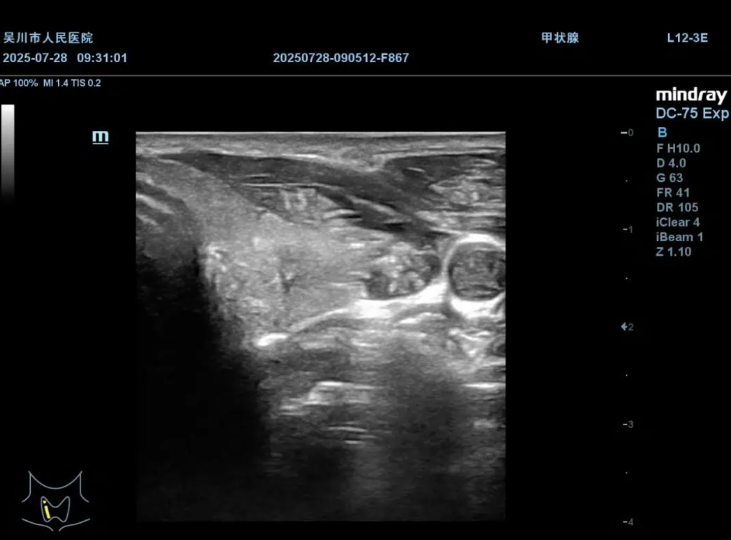

患者因体检发现甲状腺结节,在我院超声科穿刺活检,取得足够标本量,通过病理检查,确诊为甲状腺乳头状癌。

甲状腺结节

术前造影,明确结节内部情况与周围组织关系